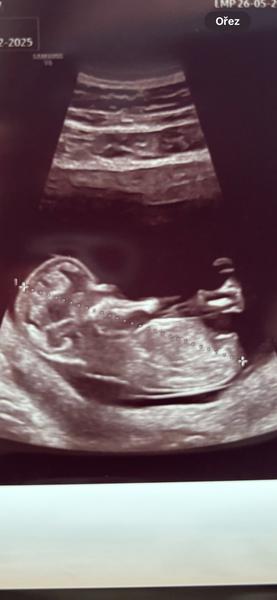

podle fotografií to vypadá spíše na pohlaví ženské, ale určitě nic nekupujte, nemalujte, apod. a vyčkejte na ultrazvuk ve 20. týdnu, protože v I. trimestru to lze jen odhadovat a často, i když to vypadá v I. trimestru jednoznačně, je ve 20. týdnu vše jinak 🙂